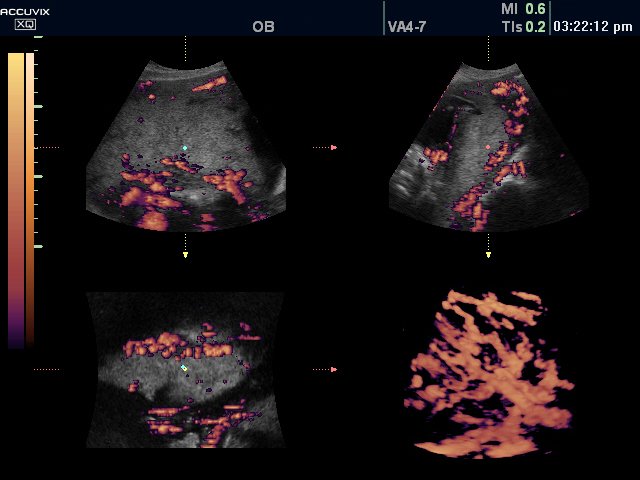

Плацента, энергетический допплер, 3D (эхограмма №319)

[EN] Эхограмма №319: Плацента в режиме энергетического картирования и 3D.

Изображение получено с помощью УЗ сканера Accuvix-XQ (снят с производства).